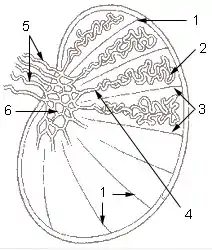

1: Testicular septa 2: Convoluted seminiferous tubules 3: Testicular lobules 4: Straight seminiferous tubules 5: Efferent ductules 6: Rete testis | |

Vertical section of the testis, to show the arrangement of the ducts.

Vertical section of the testis, to show the arrangement of the ducts. Micrograph of the rete testis involved by seminoma. H&E stain.